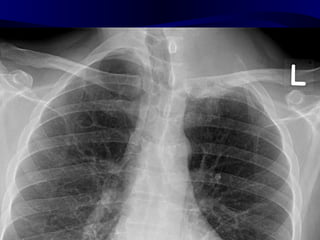

Unilateral Hilar enlargement

• Causes of hilar lymphadenopothy

– Neoplastic, e.g. spread from bronchial

carcinoma, primary lymphoma

– Infective, e.g. tuberculosis

– Sarcoidosis (rarely unilateral)

• Causes of hilar vascular enlargement

– Pulmonary artery aneurysm

– Poststenotic dilatation of the pulmonary artery

Unilateral Hilar Enlargement •Causes of hilar lymphadenopothy – Neoplastic, e.g. spread from bronchial carcinoma, primary lymphoma – Infective, e.g. tuberculosis – Sarcoidosis (rarely unilateral) • Causes of hilar vascular enlargement – Pulmonary artery aneurysm – Poststenotic dilatation of the pulmonary artery